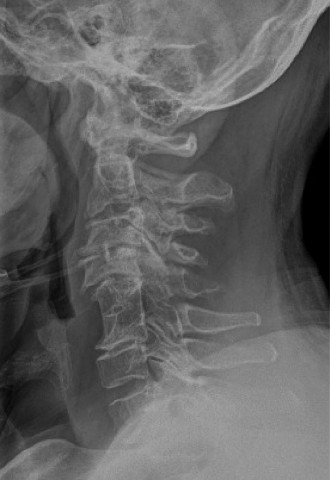

A 63-year-old male sustained a hyperextension injury to his neck while diving into a pool. Upon presentation,…